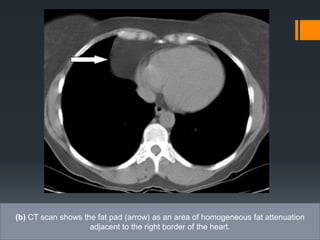

Epicardial fat pad.

(a) PA chest radiograph shows loss of the cardiac silhouette at the border of the right

side of the heart and an epicardial fat pad with relatively low density (arrow)

(b) CT scan shows the fat pad (arrow) as an area of homogeneous fat attenuation

adjacent to the right border of the heart.